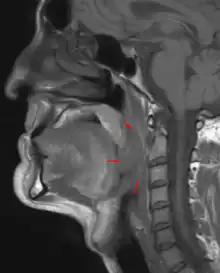

Oropharyngeal cancer

Oropharyngeal cancer,[1][2][3] also known as oropharyngeal squamous cell carcinoma and tonsil cancer,[1] is a disease in which abnormal cells with the potential to both grow locally and spread to other parts of the body are found in the oral cavity, in the tissue of the part of the throat (oropharynx) that includes the base of the tongue, the tonsils, the soft palate, and the walls of the pharynx.[1][2][3][5]